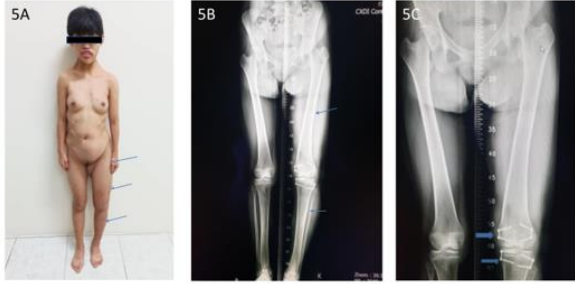

These 17 years-old girls was referred from outside hospital to Tainan Municipal An-Nan Hospital Orthopedics Department, for the purpose of tertiary consultation for progressive craniofacial dysmorphism associated with vision and hearing impairment problems. According patient’s parents’ statement she was a G2P1baby, birth date: 2007/05/24, gestation age: 40 weeks, NSD, birth height: 51 cm, birth weight: 3185 gm, head girth: 34 cm, Apgar score: 9 at one minute, 10 at five minutes, birth without obvious systemic deformity condition. Sonogram of the brain was normal at birth, with psychomotor developmental delay. Family history was non-contribution. Mild craniofacial deformity was noted by parents since the age of 2 years-old. 3D-CT image of skull revealed metopic ridge, early closure of anterior fontanelle and trigonocephaly pathologies (Figures 1A and 1B) findings at that time. Under the diagnosis of metopic craniosynostosis she received cranioplasty treatment at CGMHT P-S department aged 2+7 yrs, 2009/12/28. After the age of 3 yrs she developed slow progressive, asymmetric, segmental left lower limb overgrowth clinical symptoms, but with prominent craniofacial dysmorphism (Figures 2A-D) and associated bilateral ear hearing impairment symptoms. First menstruation at age of 12 yrs, associated with hypermenorrhea and absence of pubic and axillary hair development (Figures 3A and 3B), and spinal scoliosis problems (Figures 4A and 4B). The major operative date with Proteus syndrome related surgeries were summarized as follows. [1] PDA s/p transcatheter coli embolism treatment at CGMHT pediatric cardiology 1+3 yrs, 2008/09/24. [2] Metopic craniosynostosis s/p cranioplasty at CGMHT plastic surgery department 2+7 yrs, 2009/12/28. [3] Left leg length discrepancy 4.5 cm (2) s/p guided growth treatment (Lt distal femur and proximal tibia Orthofix 8-plate epiphysiodesis) (Figures 5A and 5B) at NTUHCH orthopedics department 14 yrs, 2021/07/05. [4] Bilateral ear canal stenosis (Figures 6A and 6B) with left ear cholesteatoma s/p left ear canalplasty + tympanoplasty + mastoidectomy+ cholesteatome excision treatment at NTUH ENT department 14+6 yrs, 2021/11/25. [5] Malocclusion, dental caries, gingival hyperplasia s/p tooth extraction, complicated odontectomy, gingivectomy at TMUH oral surgery department 15+3 yrs, 2022/03/22. Pathology report: gingival-squamous hyperplasia, alveolar bone- fibrotic osseous tissue. [6] Adenomyosis uterus with hypermenorrhea s/p hysteroscopic endometrial ablation + adenomyosis excision (Figures 7A-C) treatment at NTUH GYN department 15+8 yrs, 2022/08/22. Pathology report: endometrial hyperplasia with inactive endometrial glands and thickened submucosal tissue. [7] Left inner thigh lipoma s/p excisional biopsy at NTUHT 16 yrs, 2022/12/09. Pathology: Lipoma [8] with whole exome sequencing test. (8) Progressive and recurrent of skull hyperostosis lesions s/p forehead and orbital floor lesions partial resection at TMUH plastic surgery department 16+7 yrs, 2023/11/20. Pathology report: mature trabecular bone, with whole genome sequencing test. Postoperative patient’s problems such as: craniosynostosis, left ear hearing impairment, oral malocclusion, left leg length discrepancy, hypermenorrhea, all with partial clinical improvement. The most recent outpatient patient’s four complaints were: 1. Slow progressive craniofacial dysmorphism with neurological deficits including bilateral hearing, vision and speaking impairments. 2. 2nd sexual development delay with hypermenorrhea. 3. Overgrowth lipomatous tumors over abdomen and left lower limb. 4. Residual leg length discrepancy 2 cm. Physical examination showed significant craniofacial dysmorphism with diffused overgrowth protruding bony nodular lesions over frontal, parietal, and temporal region of the skull, hypertelorism, depressed nasal bridge, and open month disfigurations. Bilateral ear hearing loss, back hyperpigmentation skin lesion with scoliosis spinal deformity, lipomatous overgrowth tumors lesion over abdomen and left lower limb [4], residual leg length discrepancy 2 cm Lt > Rt, absent of axillary and pubic hair. Radiological Imaging both skull films and 3D-CT showed diffuse sclerotic hyperostosis lesions over the cranial outer table regions, and narrowing of bilateral auditory canal (Figure. 8A, 8B, 8C, 8D). Scanogram of spine showed thoracolumbar junctional scoliosis with lumbar megaspondyly changes (Figure.4A and 4B). Triple film of lower limb showed long bones diaphyseal dysplasia change with residual leg length discrepancy post left knee tethering growth surgery (Figure.5A and 5B). Recurrence of hearing loss of left ear, and Impairment of bilateral vision acuity was strongly complained by the patient herself recently.

Figure 5A: Disproportional overgrowth with leg length discrepancy Lt lower limb, 16 years-old. 5B. Triple film lower limb showed hypertrophy Lt femur and tibia. 5C. Post guided growth treatment of Lt distal femur and proximal tibia with 8-plate